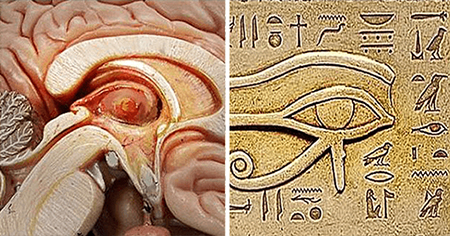

آناتومی و عملکرد غده صنوبری

غده صنوبری به شکل مخروط کاج است و به اندازه یک نخود است و قطر آن تقریباً 8 میلی متر است. در اپیتالاموس، ناحیه ای از مغز که بین دو نیمکره قرار دارد و توسط تالاموس احاطه شده است، قرار دارد. غده صنوبری از پینهآلوسیتها تشکیل شده است که سلولهای تخصصی هستند که ملاتونین، هورمونی که چرخه خواب و بیداری را تنظیم میکند، تولید و ترشح میکنند.